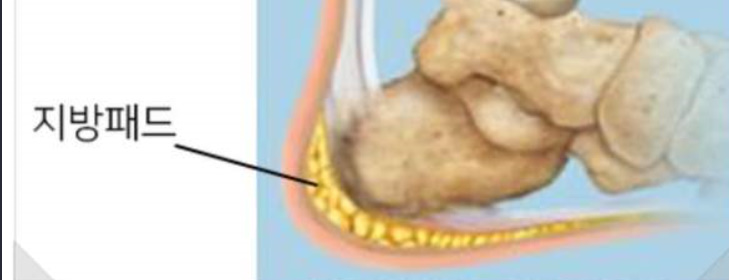

지방패드위축증후군

나이가 들면 찾아오는 발바닥 질환이다.

발바닥에는 압력을 잘 견딜 수 있도록 지방층이 잘 발달되어 있다.

이 지방층을 ‘지방패드’라 하고, 지방패드에 문제가 생기는 경우가 종종 생기는데, 주로 노화로 인하여 ‘지방패드’가 딱딱해지고 약해지면 충격을 흡수하기 어려워지고 충격이 바로 뼈로 전달되어 통증을 유발한다.